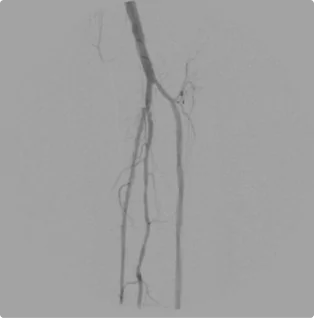

Female – Age 78

Referred by her Podiatrist for Severe Calf Pain, Non-Healing Wounds and Absent Toe Pulses

This patient had already been told by a different vascular specialist that there was nothing that they could do for her severe pain. The blockages in the arteries in her legs were so severe, no pulse could be felt in her toes. After ultrasound and evaluation, Dr. Goldstein concluded intervention was possible. Using advanced interventional techniques, He successfully cleared her arteries in both legs. Her pain subsided and her wounds healed over time. The team at Pedes Orange County regularly monitors her arterial flow to ensure she remains pain and ulcer-free.

Before

Arterial flow through the right knee and into the calf before intervention. The blockages below the knee are so severe that no clear flow exists down into the toes, causing severe pain as the muscles and tissue starve of blood.